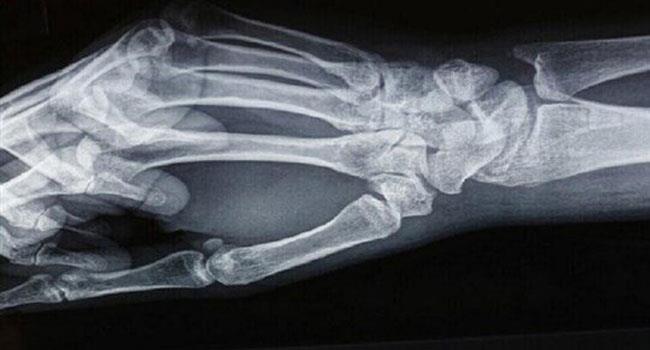

حذّر بحث جديد من أن الأنظمة الغذائية النباتية تزيد من خطر الإصابة بكسور العظام بنسبة 43% مقارنة بمن يأكلون اللحوم.

ووجدت الدراسة، التي نُشرت حديثا في مجلة BMC Medicine، والتي أجريت على ما يقارب 50000 مشارك يعيشون في المملكة المتحدة، تم تتبعتهم على مدى عقدين من الزمن أن التخلي عن لحم الحيوانات يضعف العظام، ويمكن أن يؤدي إلى هشاشتها.

ومقارنة بالأشخاص الذين تناولوا اللحوم والأسماك، وجد العلماء أن أولئك الذين يتناولون كميات أقل من الكالسيوم والبروتين كانوا أكثر عرضة لكسور الورك والساق والعمود الفقري.

وكان النباتيون أيضا أكثر عرضة بنسبة 43% للإصابة بكسور في أي مكان. وهذا ينطبق بشكل خاص على الساق والفقرات وعظم الترقوة.

ووجد البحث أن النباتيين أكثر عرضة للإصابة بالكسور الكلية ما أدى إلى ما يقرب من 20 حالة أخرى لكل 1000 شخص خلال فترة 10 سنوات مقارنة بالأشخاص الذين تناولوا اللحوم. ووجدت الدراسة أن الاختلافات الأكبر كانت في حالات كسور الورك حيث كان الخطر لدى النباتيين أكثر من ضعفي أولئك الذين تناولوا اللحوم.